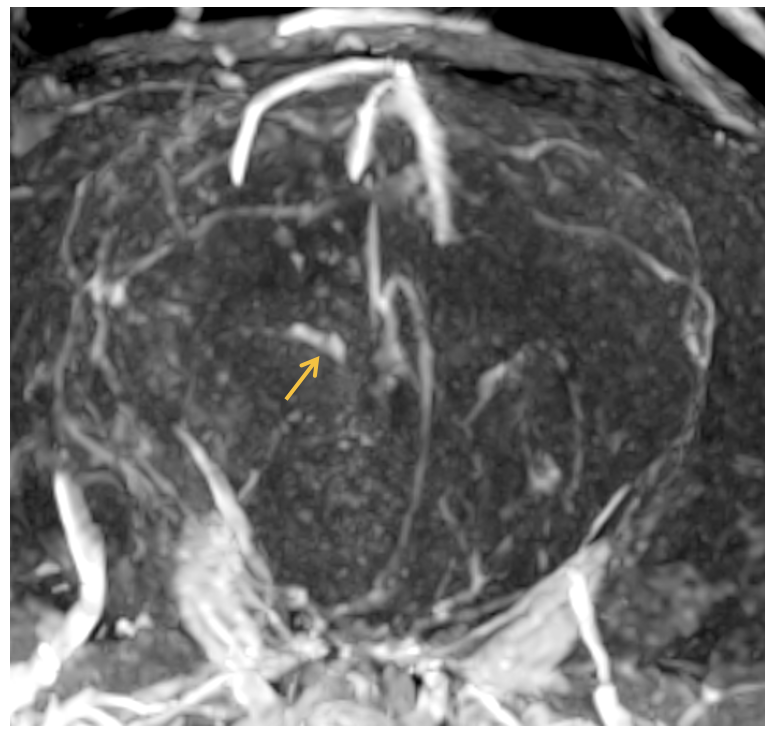

MRA(Magnetic Resonance Angiography) – 혈관 평가를 위한 전문 검사

리더스 영상의학센터는 조영제를 사용하지 않는 비조영 MRA부터 조영제를 활용한 조영 MRA까지 모두 적용하여 동물의 혈관 구조 및 혈류 상태를 보다 정확하게 평가하고 있습니다.

선천적 혈관 기형, 혈전, 동정맥 이상 등 혈관 관련 질환을 조기에 진단할 수 있으며, 수술 계획 수립 및 치료 방향 결정에 중요한 정보를 제공합니다.

또한, 환자의 상태에 따라 안전성과 정확성을 모두 고려한 최적의 방식을 선택하여 부담을 최소화하고 신뢰도 높은 검사 결과를 제공합니다.

후지 불완전 마비 보이는 환자 MRA 영상,

aortic bifurcation 및 좌측 iliac artery 내 혈전 소견

우측 대뇌 경색을 보이는 환자 MRA 영상,

우측 rostal cerebral artery 일부 확장